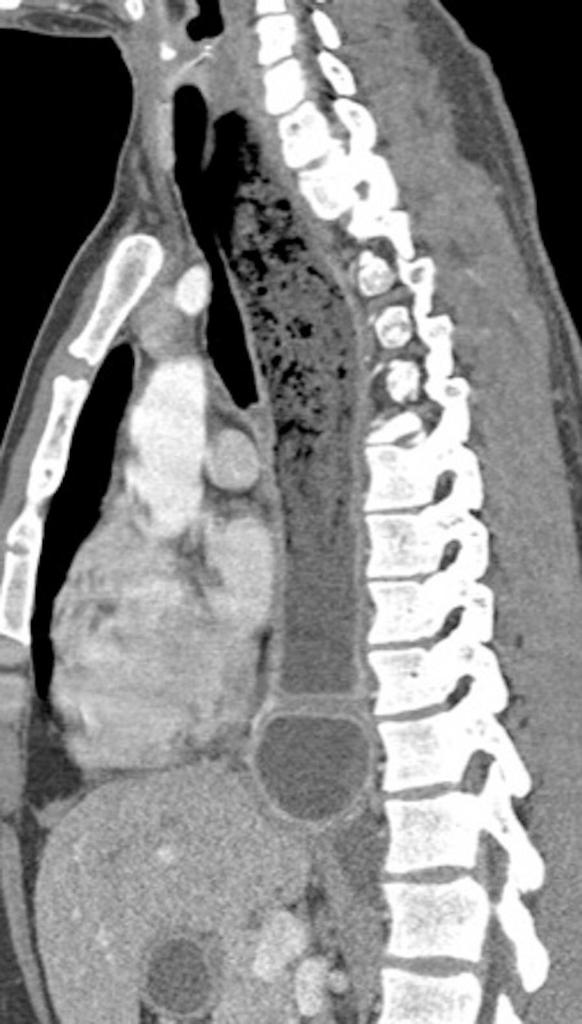

TC DE TORAX .

La Acalasia es un trastorno poco frecuente, que dificulta el paso de alimentos y líquidos hacia el estómago. La acalasia se presenta cuando se dañan los nervios del esófago. En consecuencia, el esófago pierde la capacidad de empujar el alimento hacia abajo, y la válvula muscular que se encuentra entre el esófago y el estómago( esfínter esofágico inferior) no se relaja por completo, lo que dificulta que el alimento llegue al estómago.